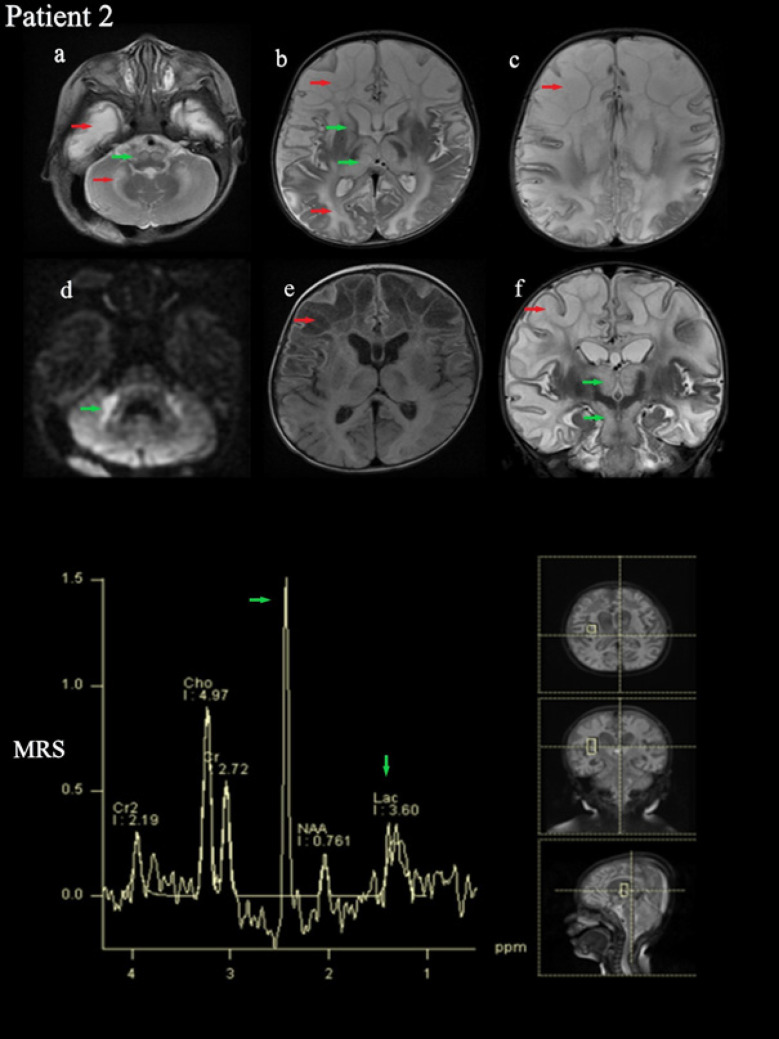

The Succinate Dehydrogenase (SDH) enzyme is known as Complex-II in the electron transport chain. This study reports the clinical and molecular investigations of three pediatric patients (two of whom are siblings), with histochemical and biochemical evidence of a severe, isolated complex II deficiency due to SDH gene mutations. The patients presented with severe hypotonia, developmental delay, spasticity, macrocephaly, and megalencephaly. Magnetic Resonance Imaging (MRI) revealed signal changes in the frontal, temporal, parietal, occipital cerebral, and cerebellar white matter, corpus striatum, thalamus, substantia nigra, inferior olivary nucleus, pyramidal tracts at the level of the pons and posterior limb of the internal capsule. Other typical findings involved a high succinate peak at 2.42 ppm and lactate peak at 1.3 ppm in Magnetic Resonance Spectroscopy (MRS). The siblings presented due to compound heterozygous c.143A>T (p. Asp48Val) and c.308T>C (p. Met103Thr) SDHB mutations, while the other patient presented due to compound heterozygous c.1754G>A (p. Arg585Gln) and c.1786G>C (p. Asp596His) SDHA mutation. The demonstration of succinate peak, particularly MRS, is highly diagnostic regarding SDH deficiency. MRS should be a standard part of routine radiological exams when there is a suspicion of a neurometabolic disease, especially mitochondrial disorders. Additionally, employing Next-Generation Sequencing (NGS) is advisable for patients as it allows for accurate diagnosis without requiring invasive procedures like muscle biopsies.